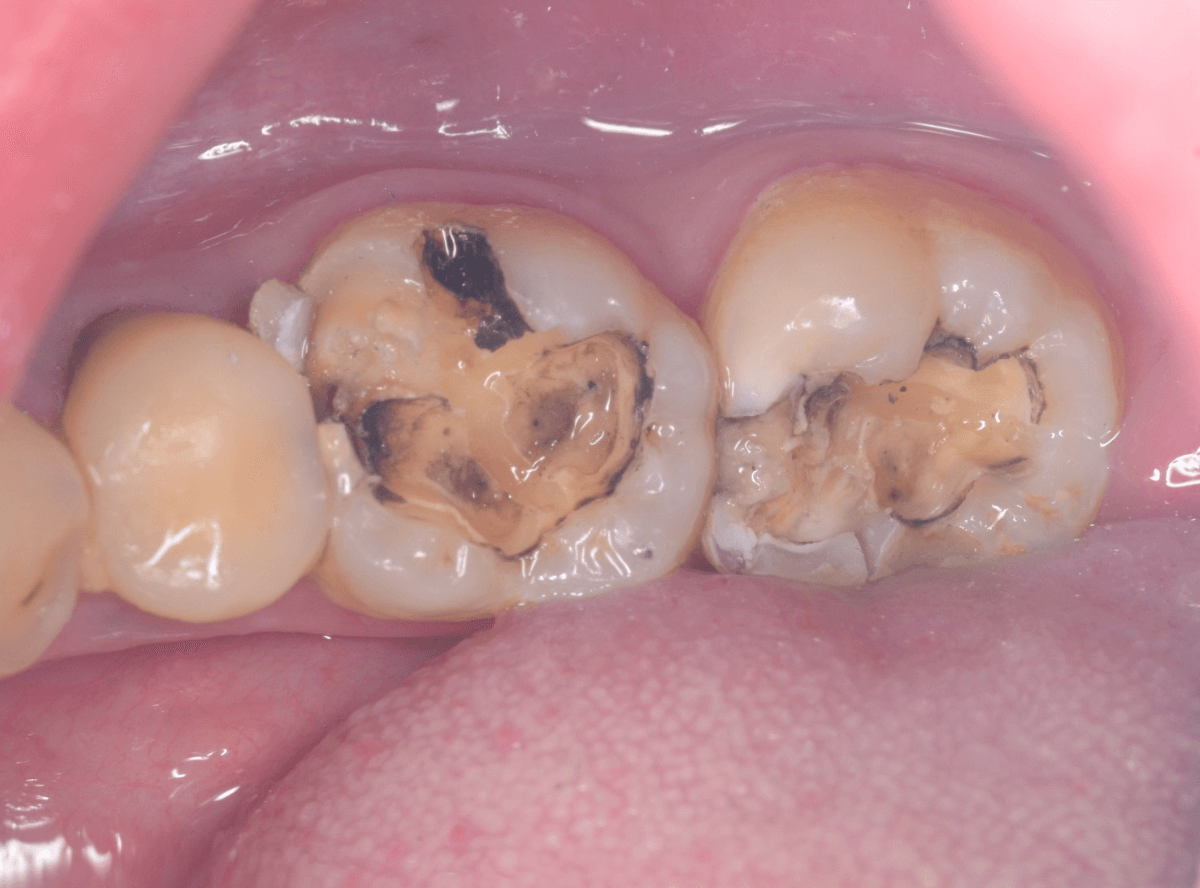

Case.16 金属の周りであちこちから虫歯

検診を希望された患者さんのケースです。

お口の中を拝見すると、上の奥歯の歯のすき間(隣接面)や、変色したレジンの中が怪しい感じです。

まず、中央の歯の金属を除去します。

〇部分は前の治療時にしいたセメントです。この下に虫歯が広がっていると思われます。

セメントを除去したところです。

赤く染め出されているところが虫歯です。

神経に近くなっていますので、診療に虫歯を除去します。

側面のレジンや隣の歯との間の虫歯も慎重に除去します。

かなり広く虫歯が広がっています。

奥の歯の虫歯も全て除去しました。

3歯すべての虫歯を除去したところです。

しばらくお薬をつめて症状を経過観察した後、型どりをしてつめものを再製作する予定です。